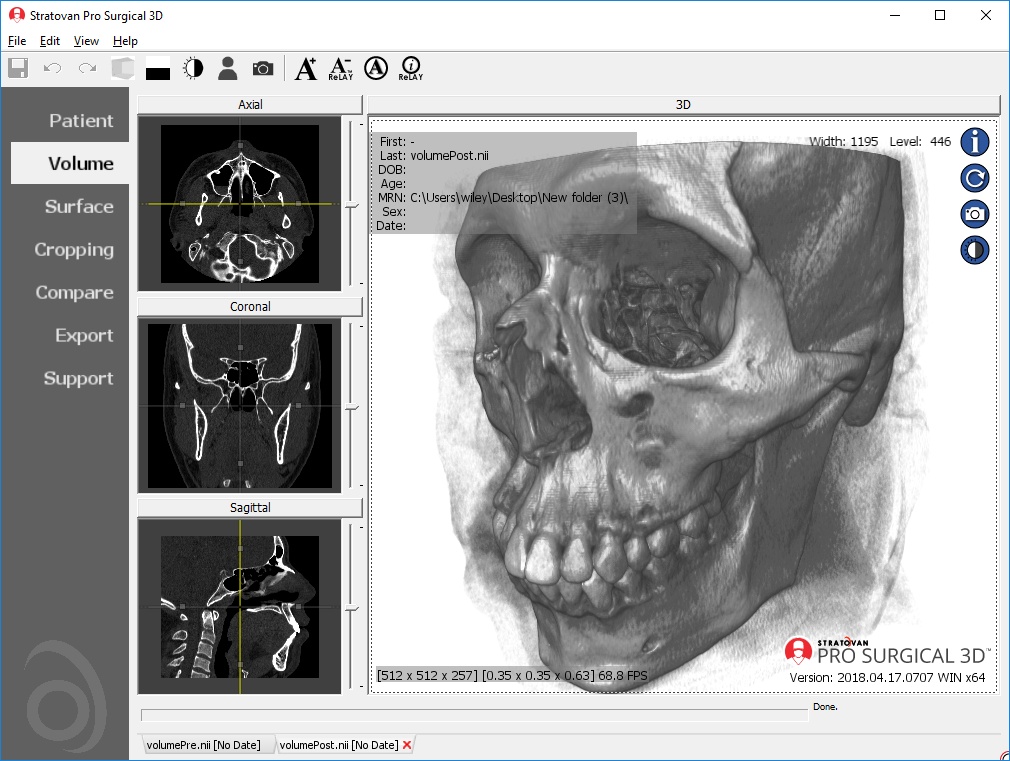

Traditional multi-planar slicing

High-quality and fast 3D reconstruction and 3D rendering

Performs 3D reconstruction and volume rendering.

Multi-planar slicing.

Side-by-side comparative assessment for pre- and post-operative scans.